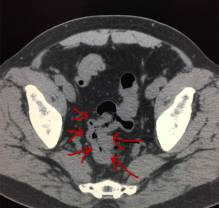

图3

如图3:这是一个未按规范做的患者,红色箭头可见未被水充盈而聚集的小肠,这时候就很容易漏了这里的病灶。而黄色箭头的是被水充盈的一小部分肠管,小肠壁是薄的。